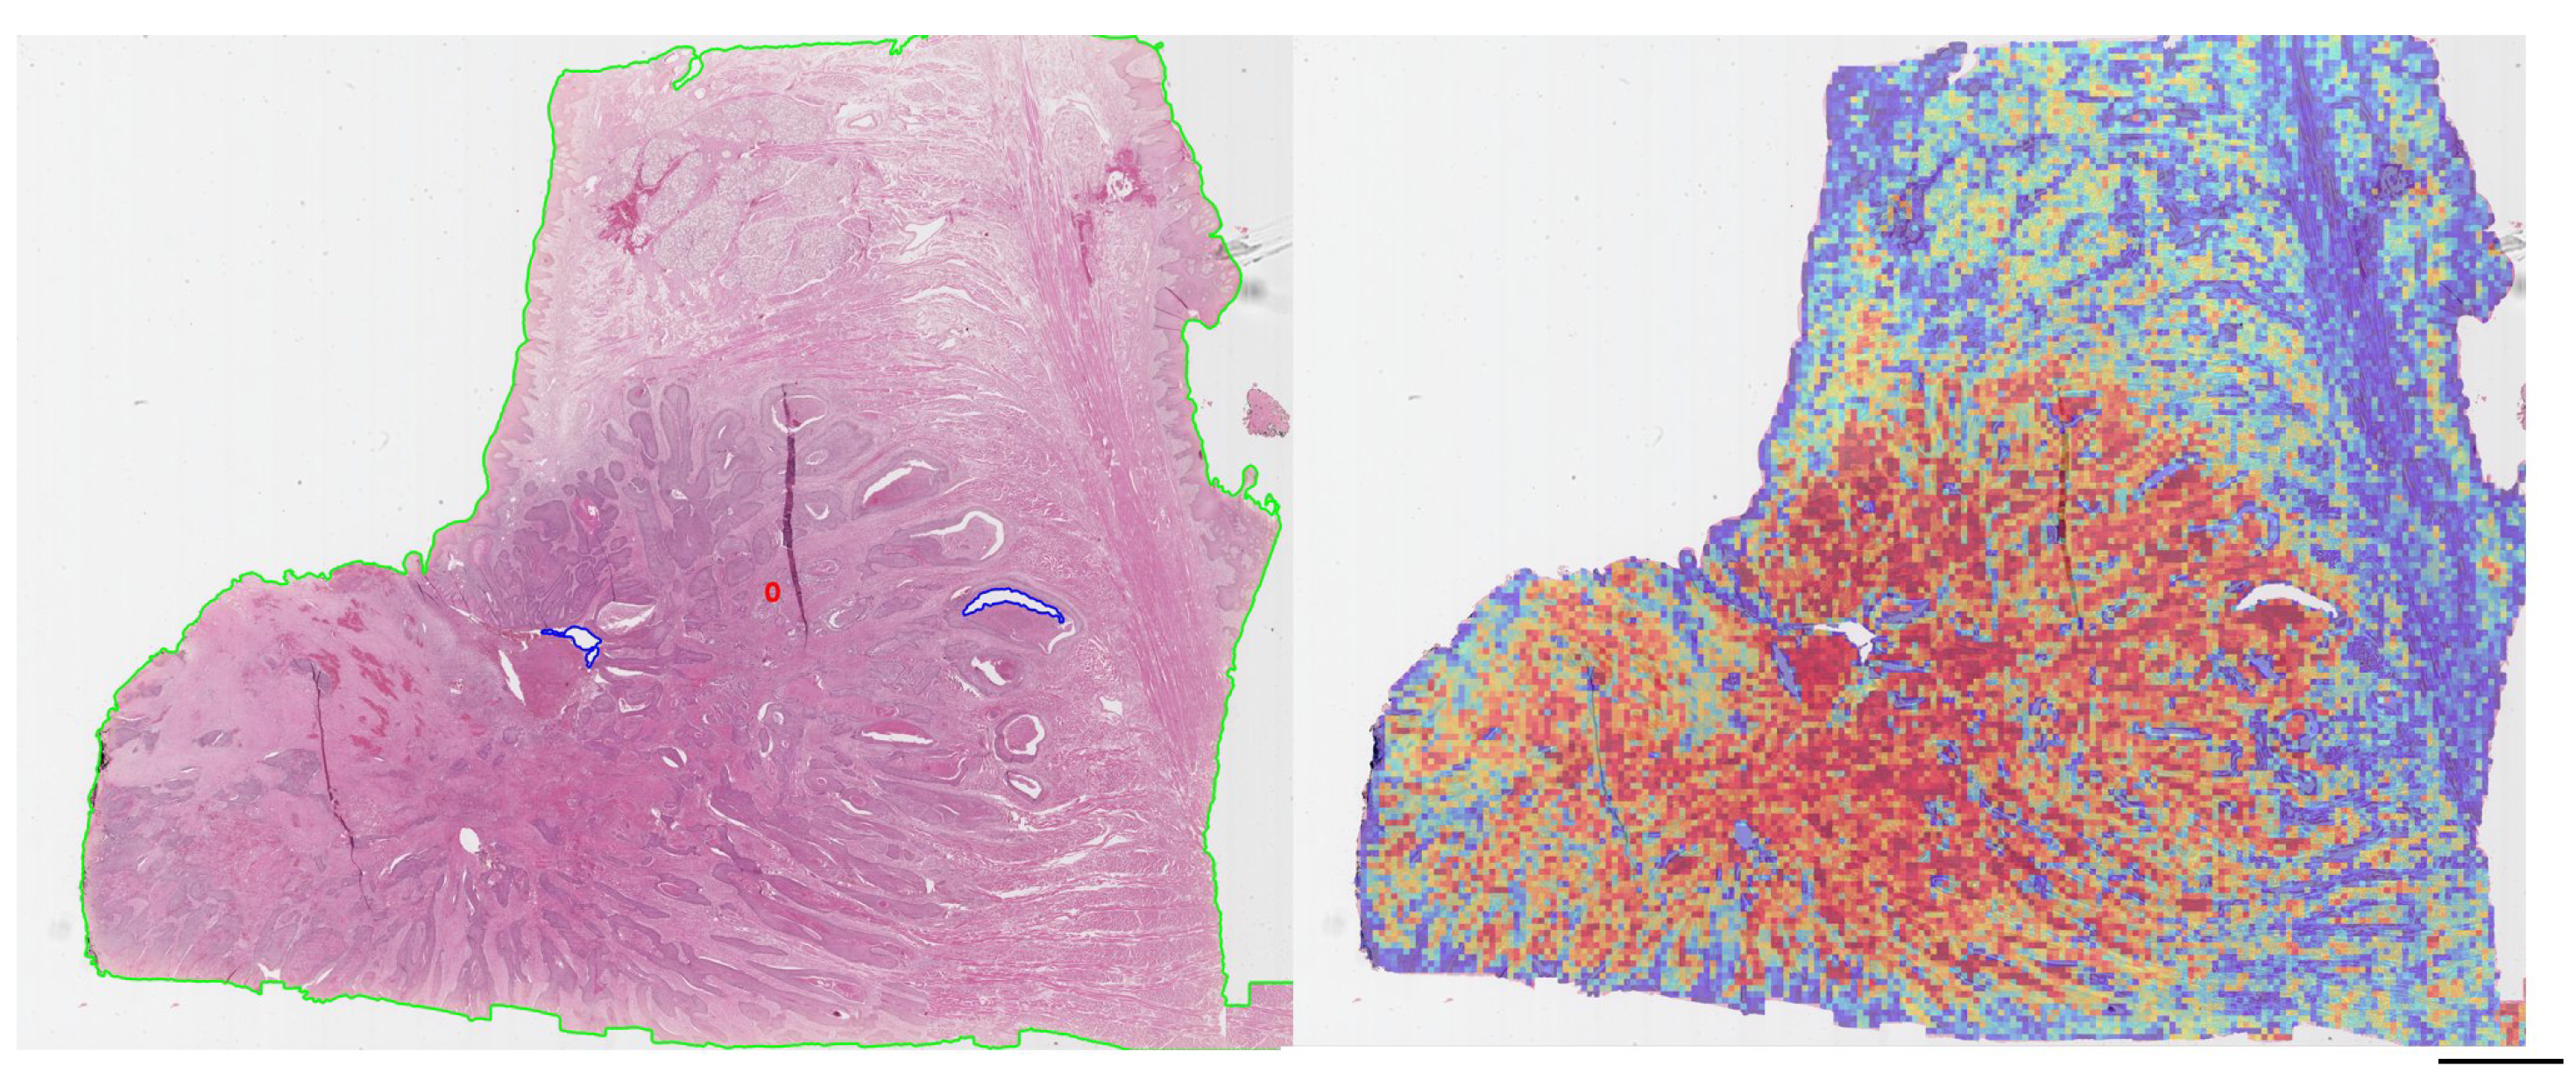

Analysis of the attention heatmaps revealed that the model consistently focused on tumor-rich regions, particularly in correctly classified cases (Figure 2 ). This behavior was observed across both training and external datasets, supporting the hypothesis that the model learns biologically relevant features for HPV status classification.

Figure 2. Representative attention heatmaps (red = high attention; blue = low attention).(100 pixel size)

Indeed, in four misclassified cases, model predictions were discordant with p16 status but aligned with INNO-LiPA results, suggesting that the model may detect histological cues more closely associated with actual HPV infection. Such findings reinforce the notion that computational models can serve as a second opinion or flag potentially misclassified cases when relying solely on p16. Technical artifacts also contributed to misclassification. Slides with tissue folds, air bubbles, or annotation markers tended to impair model performance, underscoring the need for quality control as an integral component of digital pathology workflows. To enhance model interpretability, attention heatmaps were generated. These consistently localized to tumor-rich areas across datasets, supporting the hypothesis that the model was learning biologically meaningful features. To further investigate the nature of these regions, we extracted 1,230 high-attention patches and performed supervised cell-level morphological analysis using QuPath. Over 133,000 cells were segmented and described with 41 quantitative features. A Random Forest classifier trained on these features achieved an accuracy of 82.9%, with balanced precision and recall across HPV-positive and -negative classes. These results confirm the presence of robust, class-distinguishing morphometric signals at the cellular level. Feature importance analysis revealed that the most influential variables were colorimetric, particularly haematoxylin optical density metrics associated with nuclear morphology and chromatin texture (Figure 4). Remarkably, these same features emerged as top contributors in our prior feature-based machine learning model, which was trained on manually annotated cells, suggesting strong biological consistency between traditional and deep learning approaches [15]. Overall, our findings support the potential of weakly supervised deep learning to deliver both accurate and interpretable predictions of HPV status in oropharyngeal squamous cell carcinoma (OPSCC). The reproducibility of key morphometric features, alignment with molecular results in ambiguous cases, and localization of model attention to biologically plausible regions are all hallmarks of a robust pipeline. For clinical adoption, however, seamless integration into laboratory workflows remains essential. The recent framework proposed by Angeloni et al. [21], which enables HL7-based communication between AI systems and laboratory information systems (LIS), represents a critical step toward deployment. Equally important is the integration of predictive outputs — such as heatmaps or confidence scores — into widely used platforms like QuPath to support daily diagnostic utility. In conclusion, this study demonstrates that weakly supervised deep learning can accurately and interpretably predict HPV status from H&E slides. By combining attention-based models with morphometric validation, we provide a scalable framework that complements current diagnostic standards, reduces dependence on molecular assays, and supports personalized treatment strategies for HPV-related oropharyngeal carcinoma.